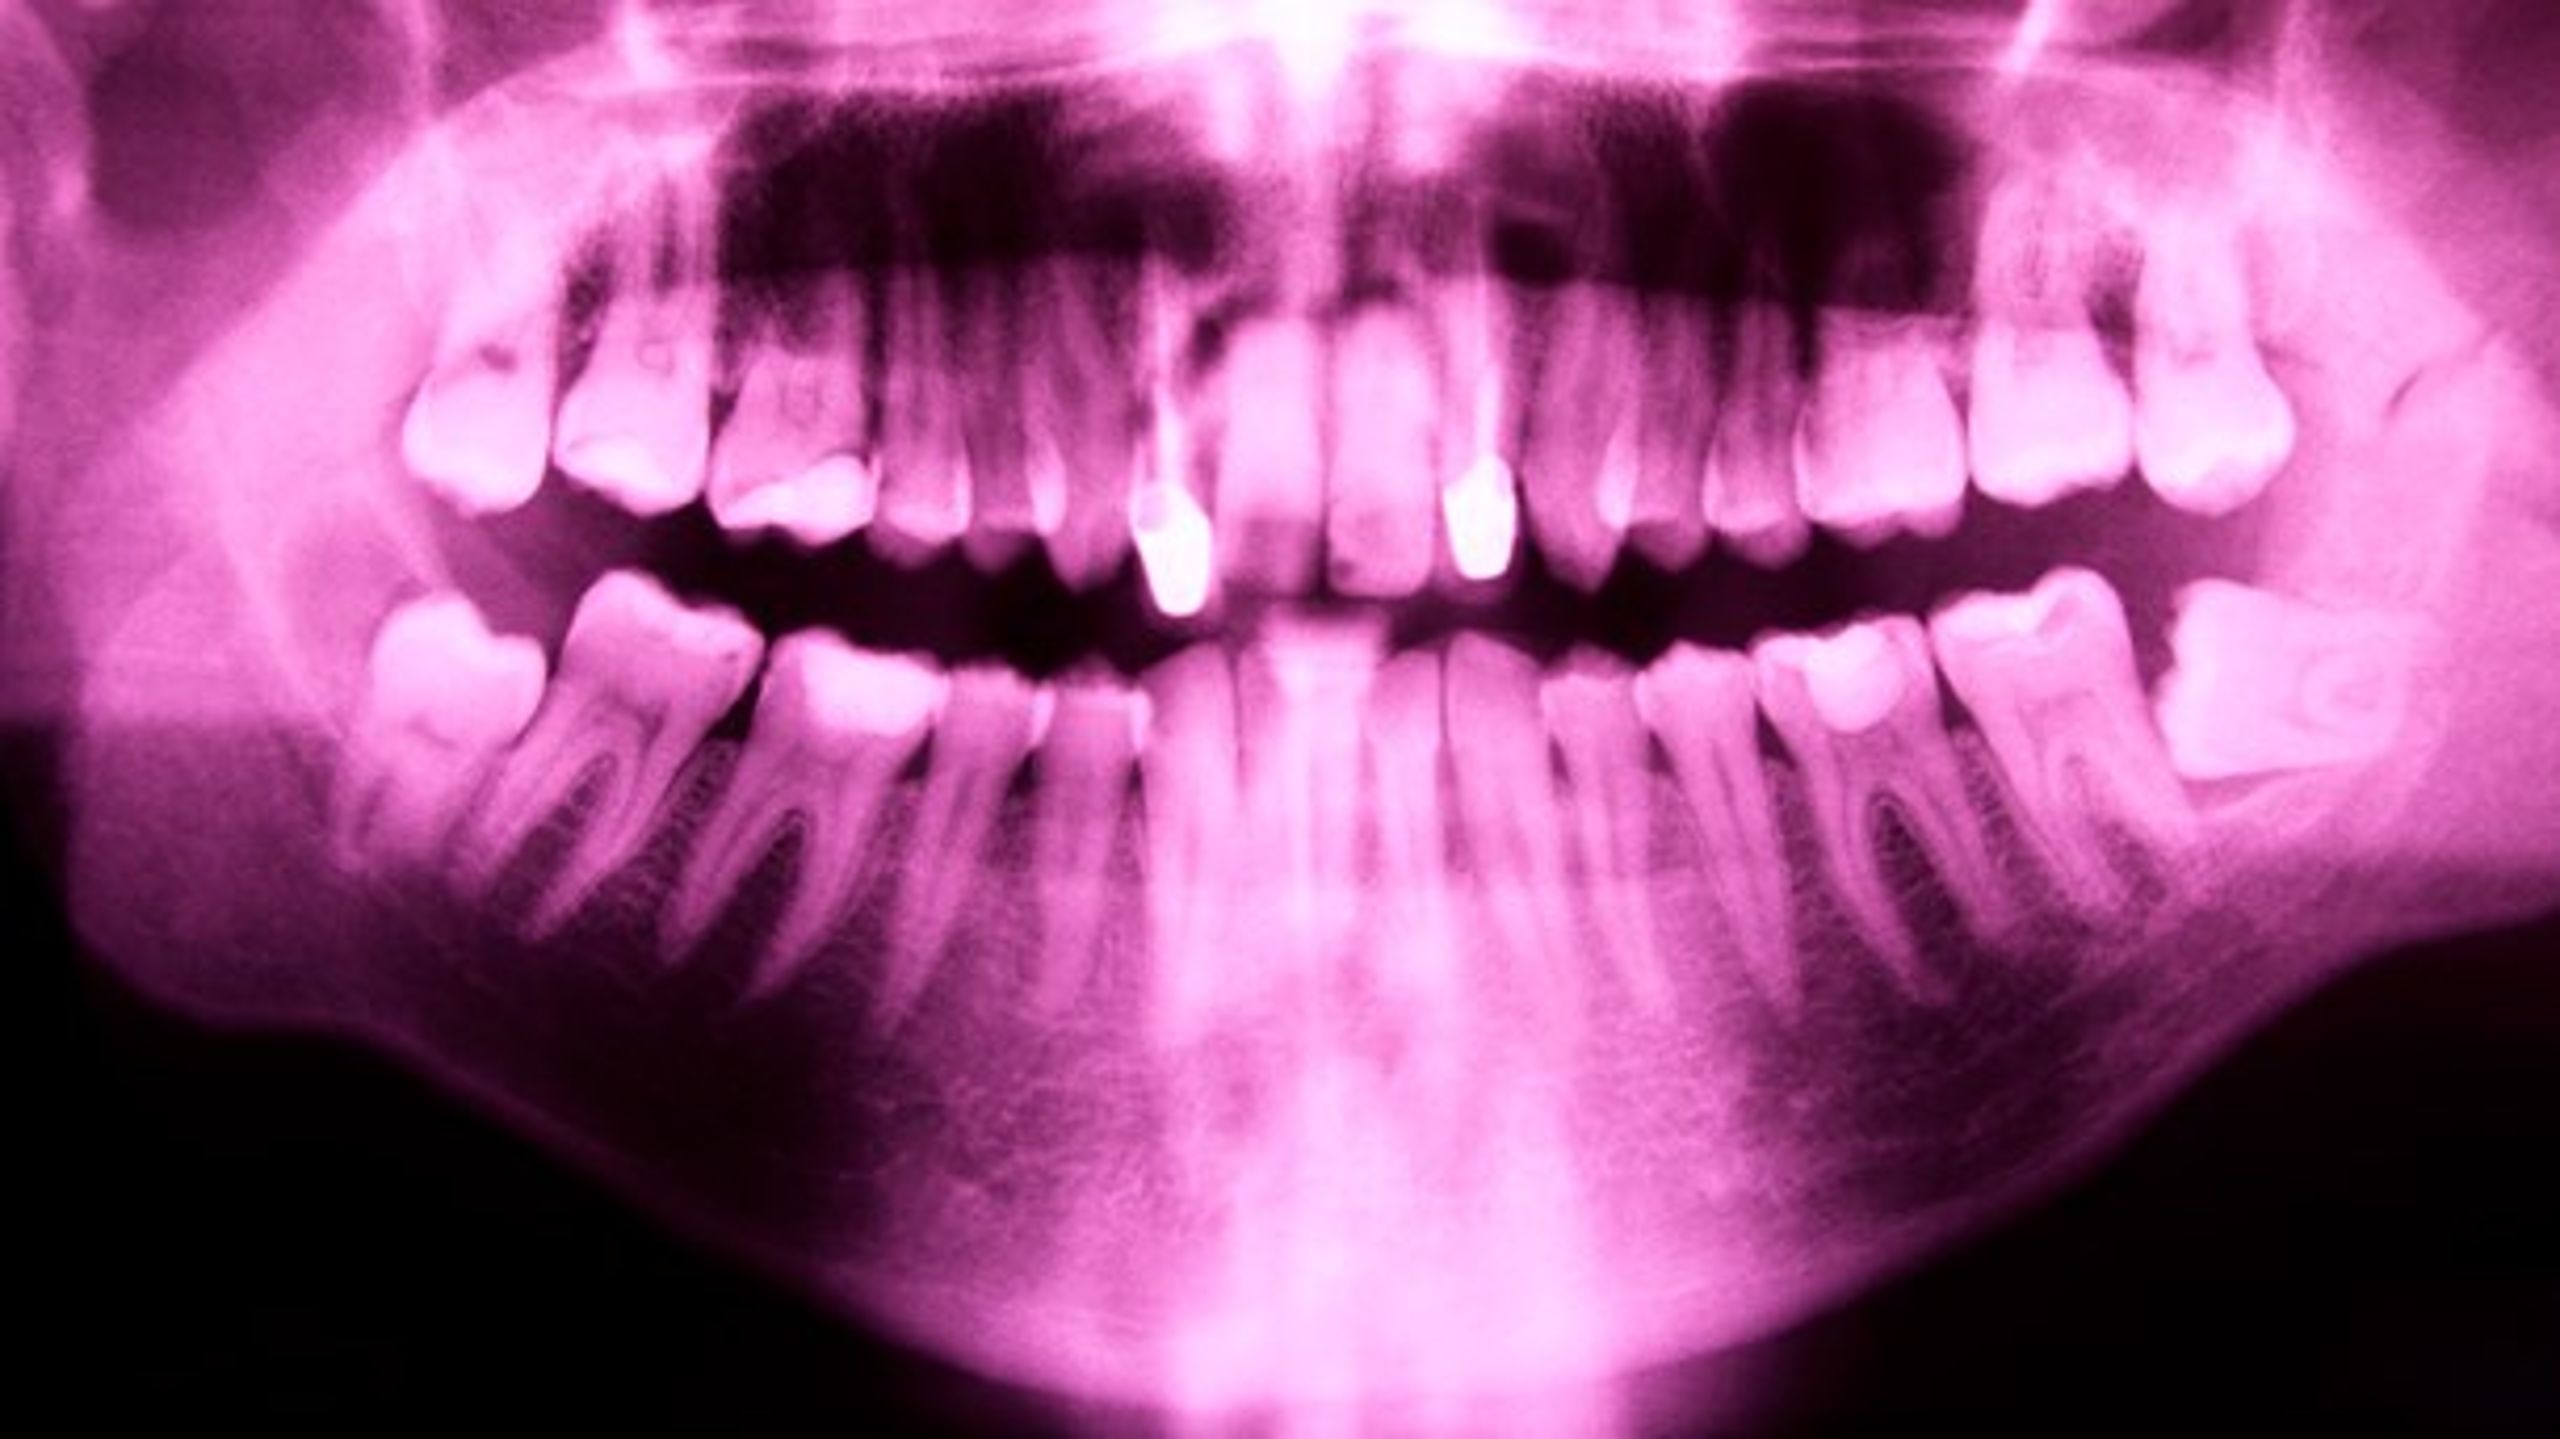

”Det første, de kigger på, er ens tænder.” Sådan sagde Jimmy til familien Danmark i DR’s omdiskuterede TV-program Blok på Bistand. Det kan være svært at forstå, og så alligevel ikke. Forestil dig, at du er arbejdsløs. Du skal til jobsamtale. Du har forberedt dig godt. Du kunne ikke have gjort mere for at være klar. Men du er stadig ikke tilpas ved situationen. For dine tænder er så dårlige, at du ikke tør smile. De afslører dig.

Scenariet er velkendt. Tusindvis af danskere lever med dårlige tænder – ofte som konsekvens af lav indtægt, der ifølge Ugebrevet A4 er den faktor, som har størst indflydelse på, om man gentagende gange springer tandlægebesøget over.

Jeg hørte engang en sige, at hvis man vil vide, hvor mange penge et menneske har, er det bedste sted, man kan kigge, i personens mund. Jeg synes, det siger en del. Der er en ekstrem ulighed i sundhed på tandlægeområdet i Danmark. Som Jimmy selv tilføjede: ”Hvis du har dårlige tænder, så har du dårlige muligheder.”

Det er på tide, at vi kommer uligheden til livs. Og det behøver faktisk ikke være så svært. I dag er det gratis at gå til tandlæge, hvis man er under 18 år. Jeg foreslår, at vi udvider ordningen til at gælde alle danskere uanset alder. En lille revolution i vores sundhedssystem, der vil gøre en kæmpe forskel for os alle – særligt de mest udsatte i Danmark.

Det er svært at finde et godt argument for, hvorfor vi i Danmark har valgt, at hvis man får en fysisk sygdom, så har man ret til gratis behandling – medmindre at det er en tandsygdom.

Tandlægebehandling er i virkeligheden på mange måder præcis som al anden lægebehandling vi får – forskellen er blot, at tandlægebehandling koster kassen for den enkelte.